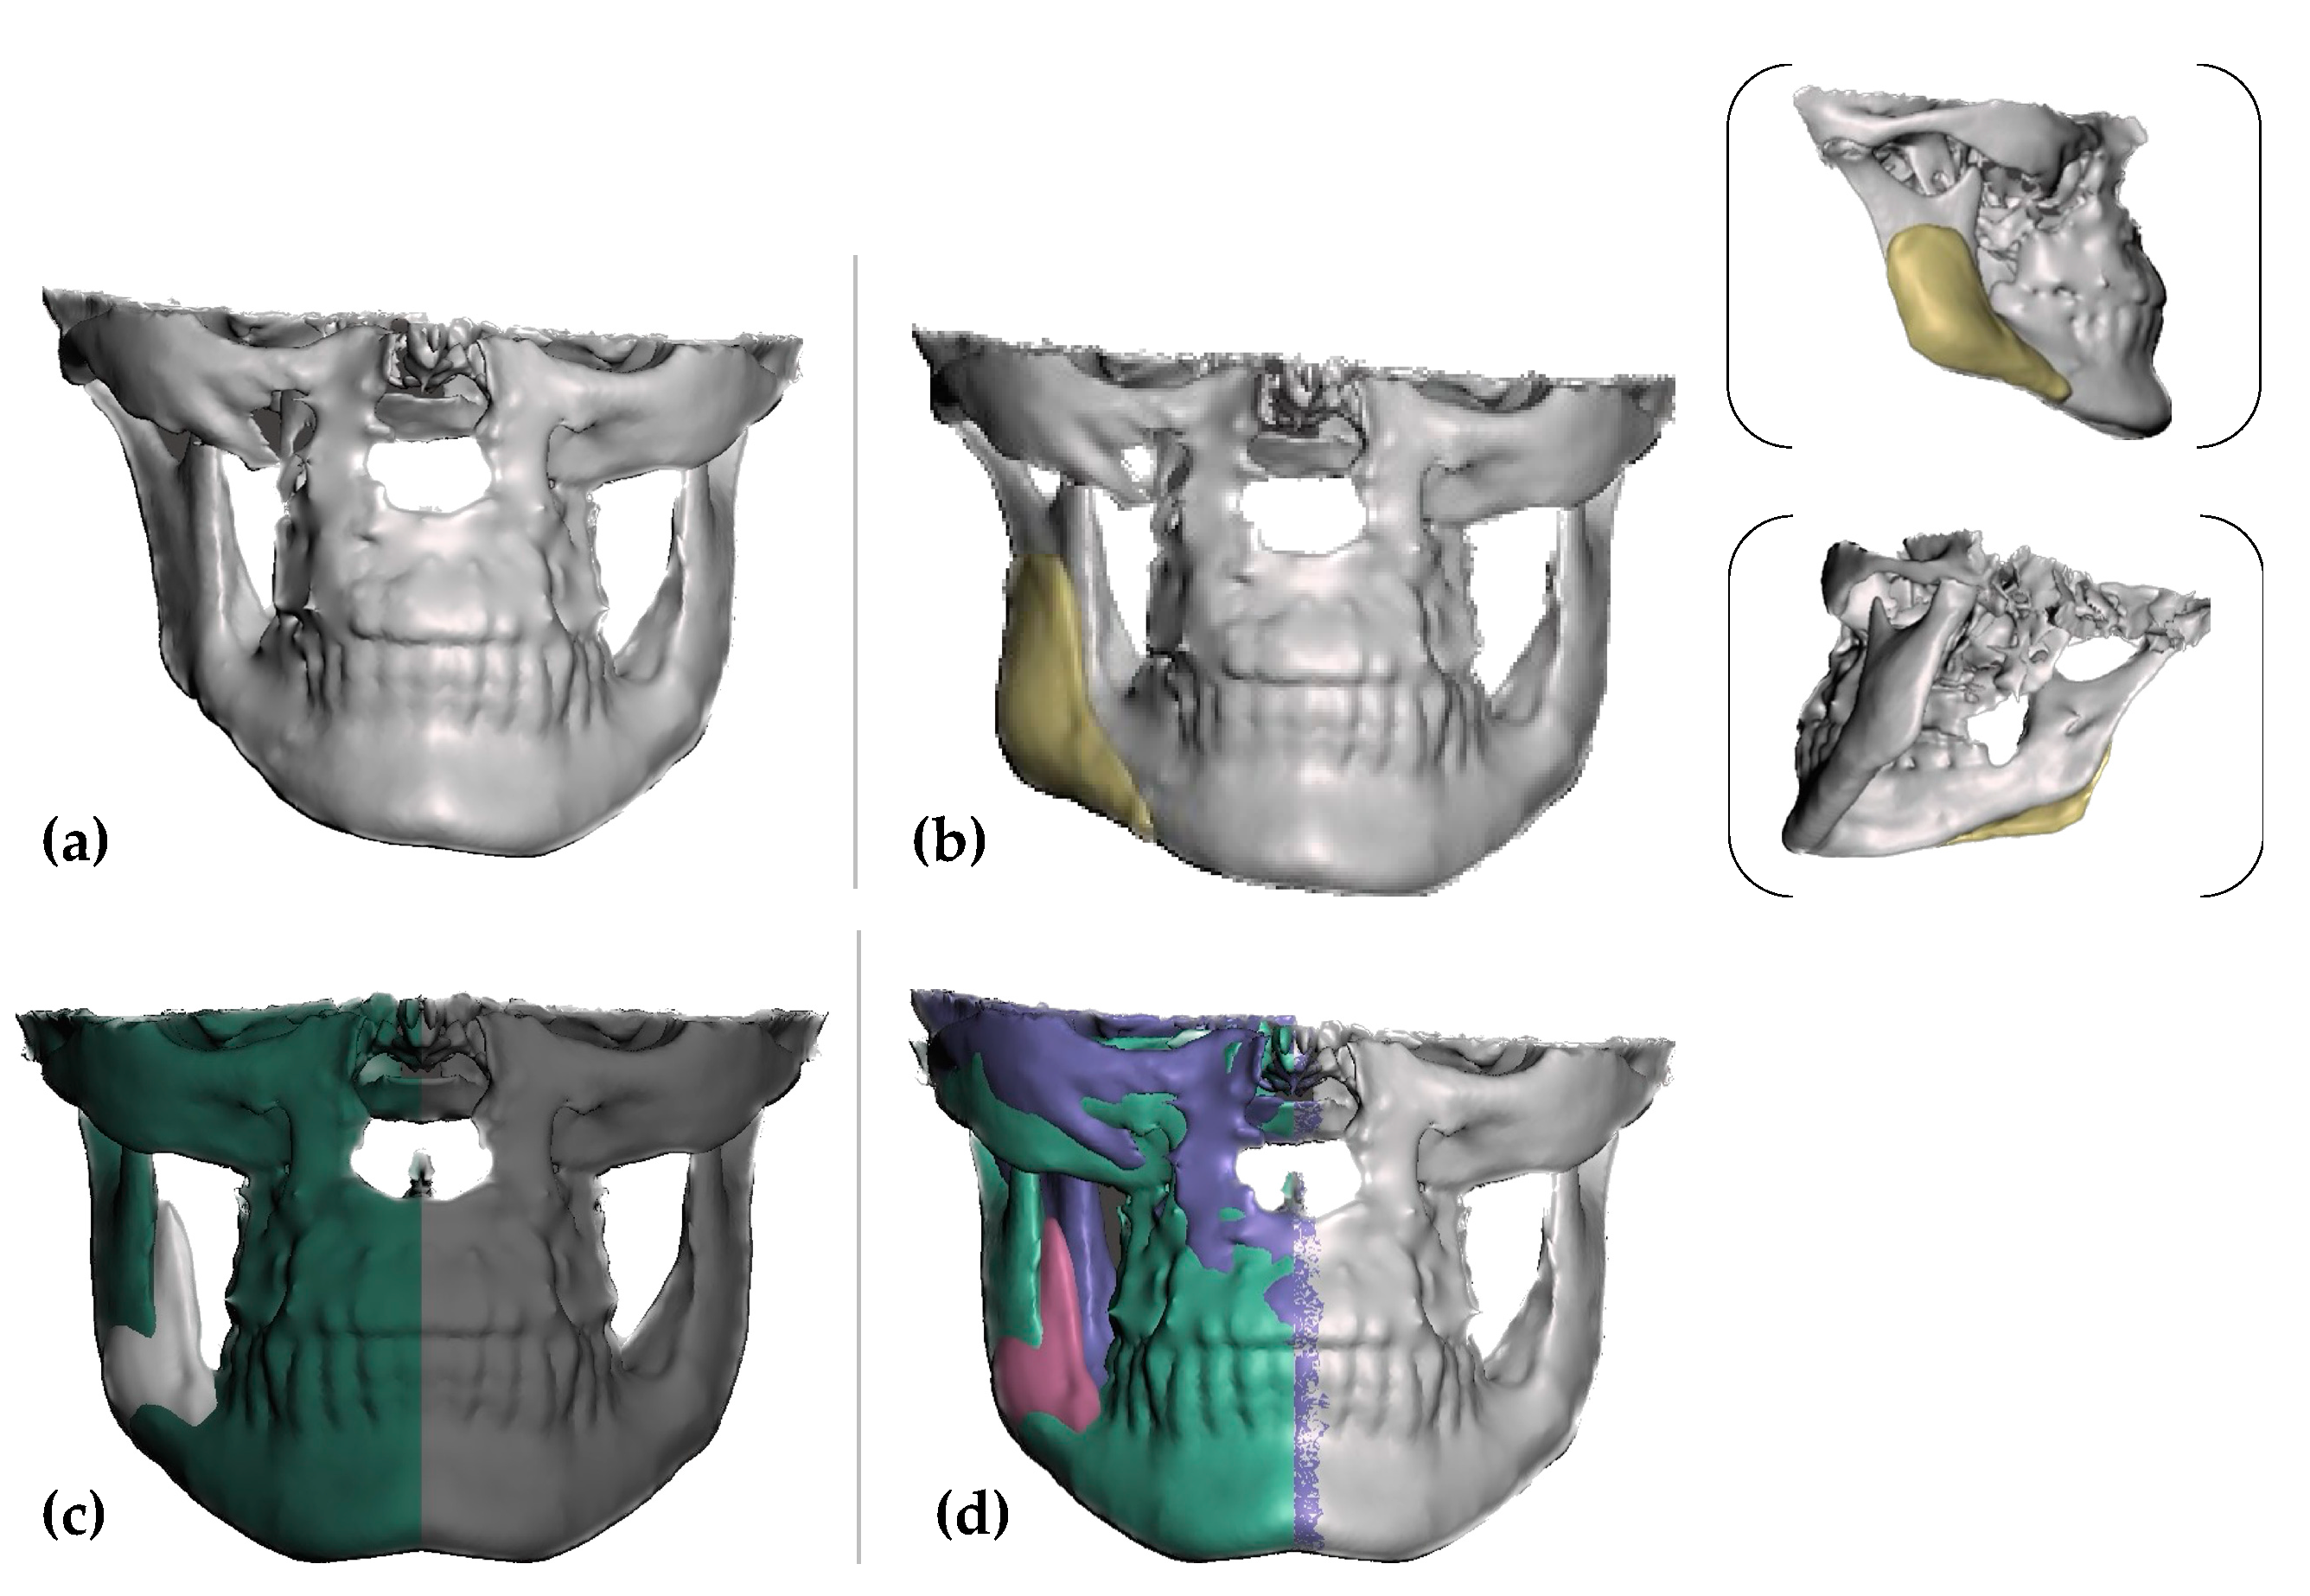

2. Case Report

2.1. PSI’s Mold Design and Fabrication